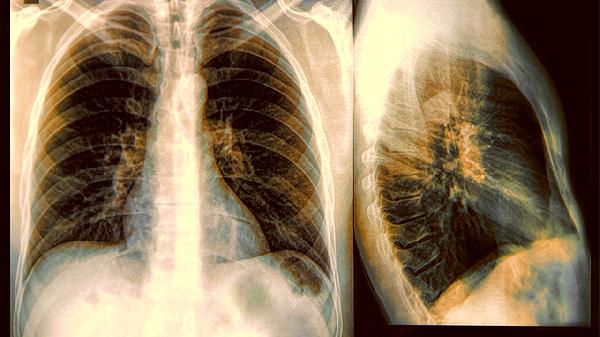

常规体检中的胸片检查虽然能发现部分问题,但对于早期病变检出率有限。高危人群可以考虑更精确的检查手段。